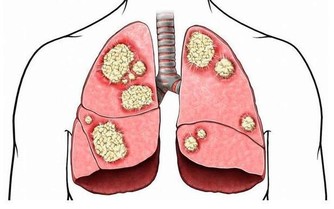

調查結果顯示,吸煙或者吃烤肉等在體內聚集的強致癌物質多環芳香烴,

在喝紅酒後會顯著降低,特別是喝了100%葡萄原汁的紅葡萄酒。